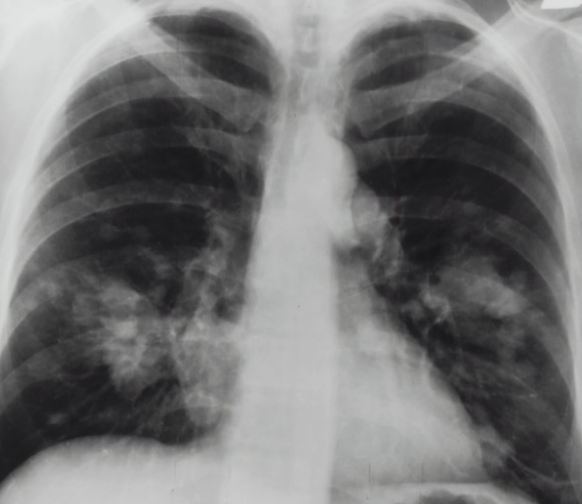

녹차의 폐암 예방 효과에 대한 연구 결과가 있습니다. 대만 충산(中山) 의학대학 연구팀이 진행한 연구에 따르면, 흡연자와 비흡연자 모두에게 녹차가 폐암 발생 위험을 낮춰주는 효과가 있다는 것입니다.

연구팀은 폐암 환자 170명과 건강한 사람 340명을 대상으로 조사를 실시했습니다. 그 결과, 녹차를 전혀 마시지 않는 사람과 하루에 1잔 이상 마시는 사람을 비교했을 때, 폐암 발생 위험은 평균적으로 5배나 높은 것으로 나타났습니다. 또한, 흡연자의 경우 녹차를 전혀 마시지 않는 사람에 비해 하루에 1잔 이상 마시는 사람의 폐암 위험이 13배나 높다는 결과도 있었습니다.

이러한 효과는 녹차에 함유된 강력한 항산화 성분인 폴리페놀에서 나타나는 것으로 연구팀은 밝혔습니다. 녹차에는 폴리페놀이 풍부하게 포함되어 있으며, 이 성분은 특히 강력한 항산화 작용을 가지고 있어 종양 형성을 억제하는 효능이 있다고 알려져 있습니다.

이 연구 결과는 미국암연구학회(AACR)와 국제폐암연구학회(IASLC)가 공동 주최한 폐암 학술회의에서 발표되었습니다. 이러한 연구들은 녹차가 폐암 예방에 긍정적인 영향을 미칠 수 있다는 가능성을 제시하며, 폐암 예방을 위해 녹차의 소비를 고려하는 데 도움을 줄 수 있습니다.목차